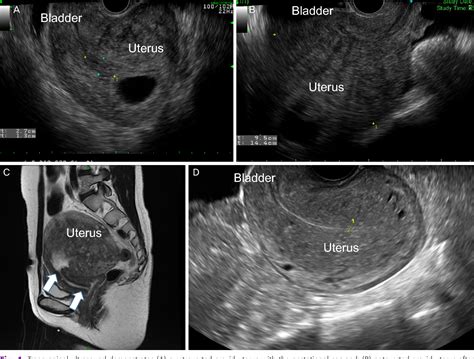

Ultrasound Imaging

Ultrasound imaging is a non-invasive technique that uses high-frequency sound waves to create images of the uterus and fetus. It is commonly used to:

• Confirm the presence of a gravid uterus

• Determine the gestational age of the fetus

• Assess fetal development and growth

• Identify any potential abnormalities or complications

Ultrasound examinations are typically performed at various stages of pregnancy to monitor the fetus's progress and detect any issues early.